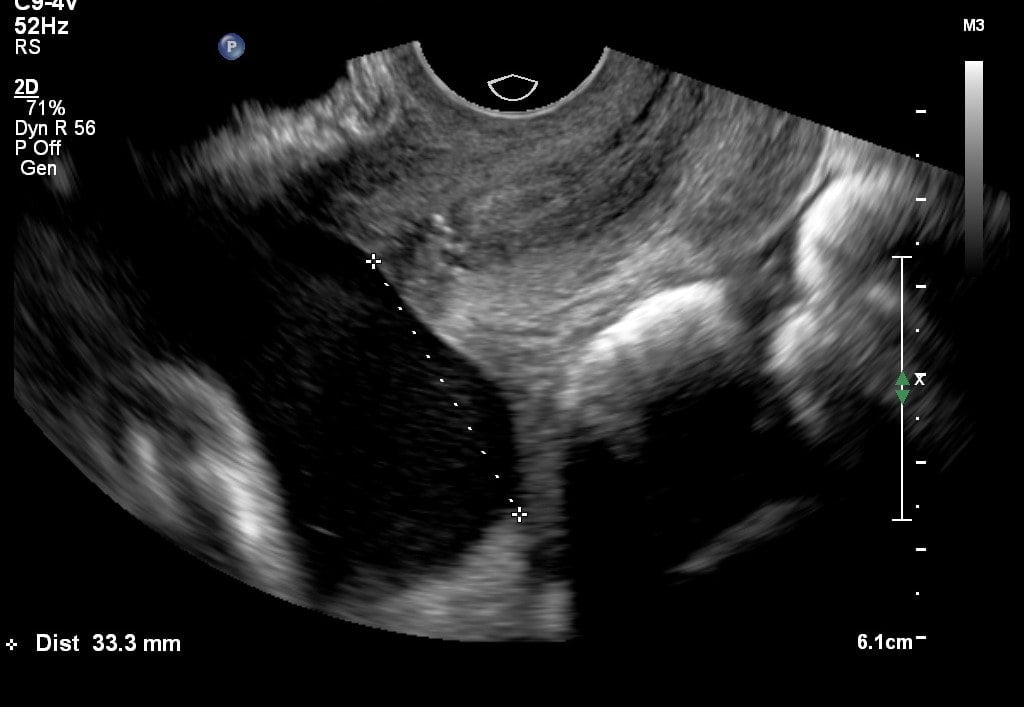

In de meeste gevallen is de placenta voldoende omhoog gegroeid. Dit gebeurt in de zwangerschap met de groei van de baarmoeder. Bij 32 weken willen wij dat de placenta minimaal 2 centimeter bij de baarmoederhals vandaan ligt, omdat je anders risico op complicaties loopt.

Deze echo is zowel via de buik als via een inwendige vaginale echo, omdat de baarmoedermond goed in beeld gebracht moet worden. De verloskundige vertelt je er meer over op het spreekuur.